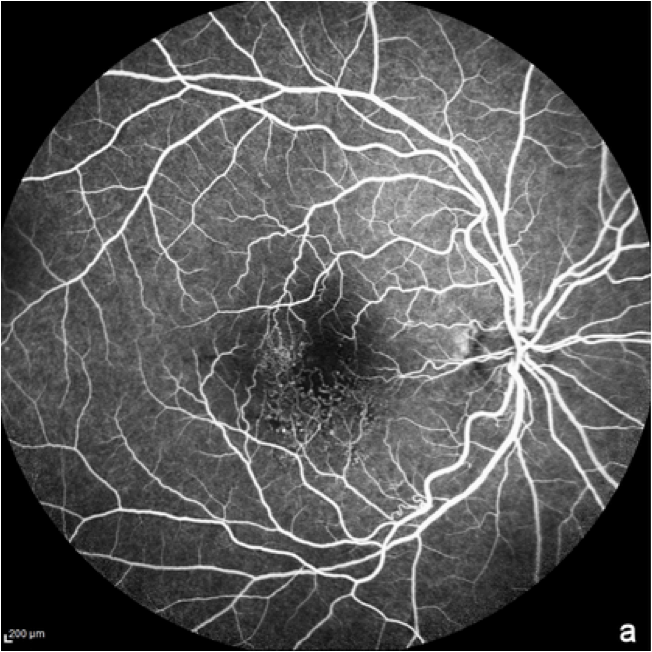

Fluoreszenzangiographie des Augenhintergrunds (FA)

Bei der Fluoreszenzangiographie wird ein fluoreszierender Farbstoff intravenös verabreicht, um eine bildliche Darstellung der Blutgefäße der Netzhaut zu ermöglichen.11 Die FFA wird in der Regel verwendet, um das Vorliegen einer feuchten AMD auszuschließen. Sie kann auch bei fortgeschrittener trockener AMD oder geographischer Atrophie eingesetzt werden, da atrophische Regionen aufgrund des Absterbens des retinalen Pigmentepithels (RPE) eine erhöhte Fluoreszenz aufweisen.8

Die Bildgebung mittels FFA zeigt Details der Netzhautgefäße sowie den Abbau des Farbstoffs in normalen Teilen der Netzhaut und die anhaltende Fluoreszenz in Bereichen mit Netzhautanomalien.12